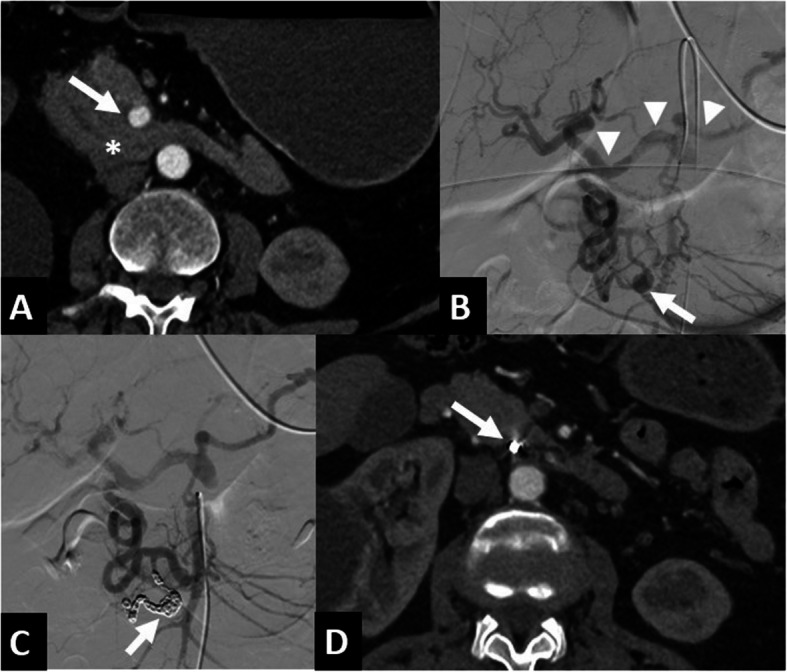

Background: The aim of this single-center retrospective study is to evaluate the feasibility, complications, and outcomes of transarterial embolization (TAE) for ruptured pancreaticoduodenal arcades aneurysms (PDAAs) due to median arcuate ligament (MAL), without subsequent revascularization of celiac artery (CA) occlusion/stenosis.

Methods: Between January 1st 2012 and June 1st 2024, all records from adult patients (≥ 18 years old) referred to our hospital for TAE due to ruptured PDAAs were retrospectively reviewed. All referrals were based on emergency clinical decisions and computed tomography. Procedure data included procedure, type of embolic agent and per-procedural complication. TAE technical success was defined as the cessation of aneurysm opacification immediately after the TAE, based on angiographic findings. Overall technical success was defined as the cessation of aneurysm opacification after TAE or percutaneous salvage approach during the same session. Then, we analyzed all published original articles published between January 2007 and December 2024 on emergency TAE of ruptured PDAAs due to MAL, without subsequent treatment of CA stenosis/occlusion.

Results: Nine patients (4 males) were referred for TAE for ruptured PDAAs due to MAL in our center. TAE technical success was achieved in 7/9 patients, and overall technical success was achieved in all patients. There were no major complications. No patients had rebleeding during follow-up. We reviewed four retrospective studies including 29 patients treated for ruptured PDAAs due to MAL without subsequent treatment of CA stenosis/occlusion. No patient received additional treatment for CA stenosis/occlusion. No aneurysm recurrence was diagnosed during the reported follow-up periods ranging from 1 to 65 months.

Conclusion: TAE for ruptured PDAAs without CA revascularization is safe and should be considered, although further studies are required to validate its validity and long-term outcomes.